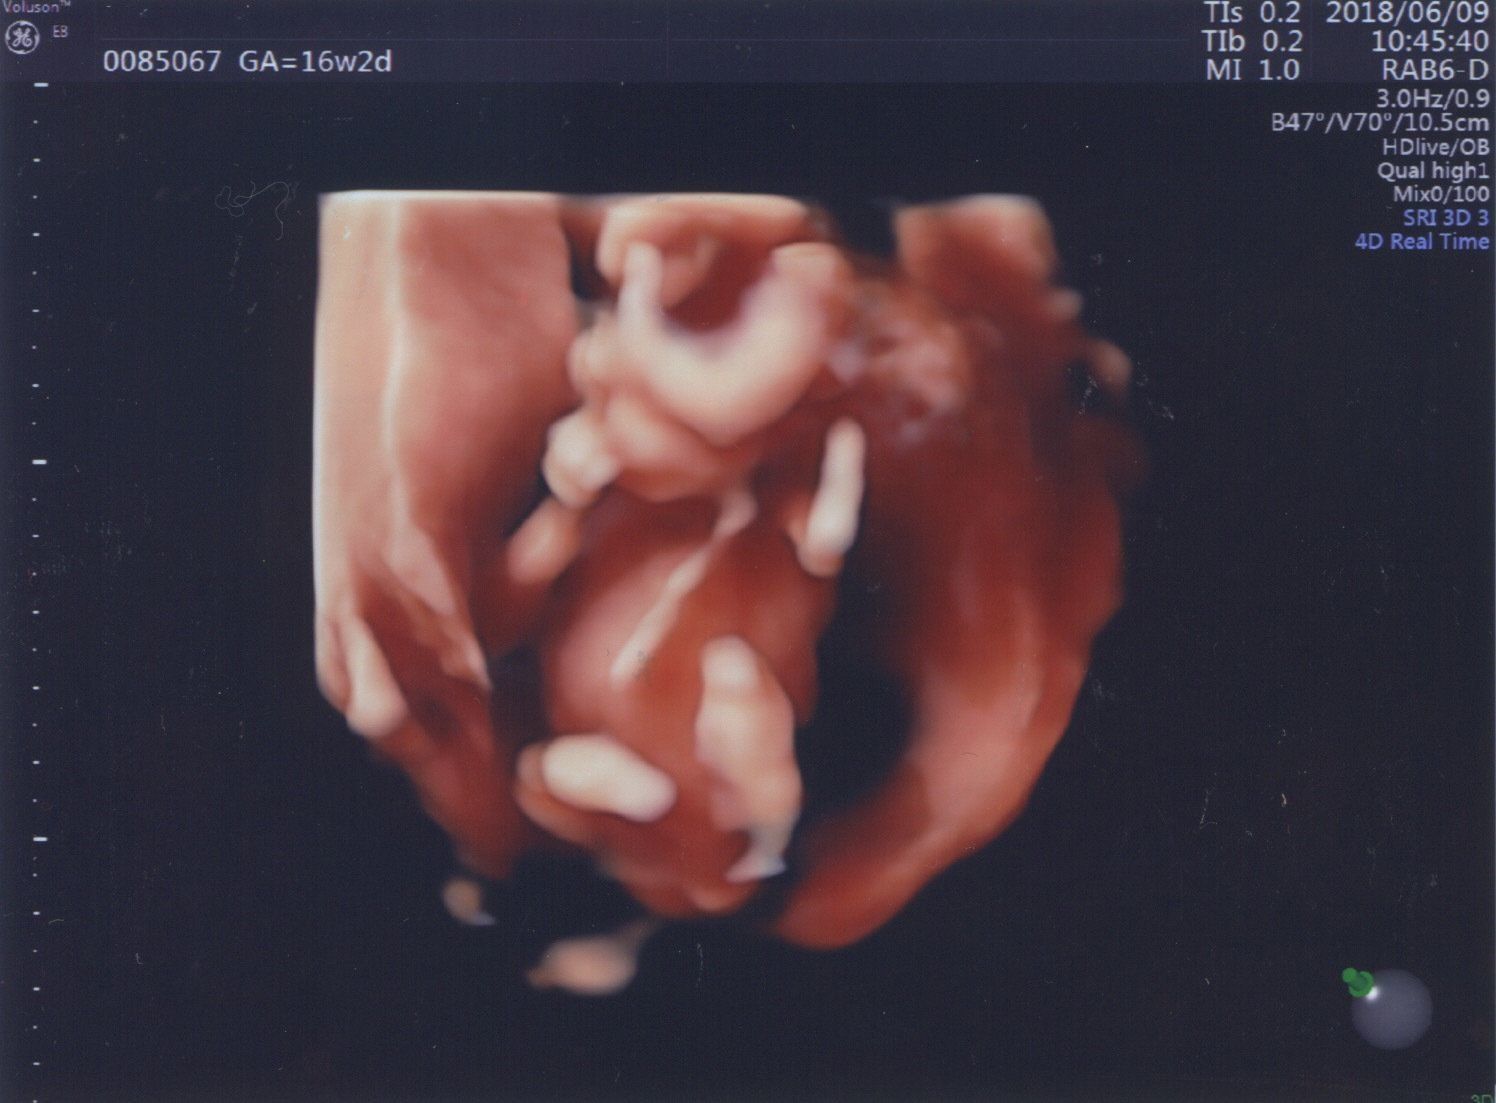

妊娠16週目 安定期に入り両親にも報告

妊娠16週目の健診。目や鼻もよくわかるようになりました。エコーの最中も元気よく動いていて、パッと小さな手を開いてかわいい指を見せてくれました。